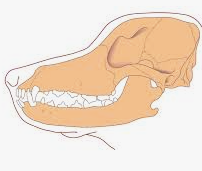

骨折

骨折 胸骨の骨折(fractures of the sternum) ~ 大動物・小動物

大動物胸骨の骨折は、杭・垣根・枠場にひっかかる、垣根を跳び越える、激しい衝突、交尾などが原因となって発生しますが、非常に稀な事故です。胸骨瘻が継発することがあります。新鮮な皮下骨折は、X線検査によらないと判明しないことがあります。外見上は、...